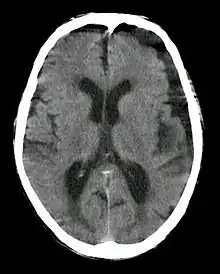

Subdural hygroma, frontal and temporal. Man of 80 years old.

In CT scan, subdural hygroma will have same density as the normal CSF. Meanwhile, in MRI, subdural hygroma will have same intensity with CSF. If iodinated contrast is administered during CT scan, the hygroma will produce high density because of the contrast at 120 kVp. However, at 190 kVp, hygroma with contrast will have intermediate density.[2]

It is not uncommon for chronic subdural hematomas (SDHs) on CT reports for scans of the head to be misinterpreted as subdural hygromas, and vice versa. Magnetic resonance imaging (MRI) should be done to differentiate a chronic SDH from a subdural hygroma, when clinically warranted. Elderly patients with marked cerebral atrophy, and secondary widened subarachnoid CSF spaces, can also cause confusion on CT. To distinguish chronic subdural hygromas from simple brain atrophy and CSF space expansion, a gadolinium-enhanced MRI can be performed. Visualization of cortical veins traversing the collection favors a widened subarachnoid space as seen in brain atrophy, whereas subdural hygromas will displace the cortex and cortical veins.